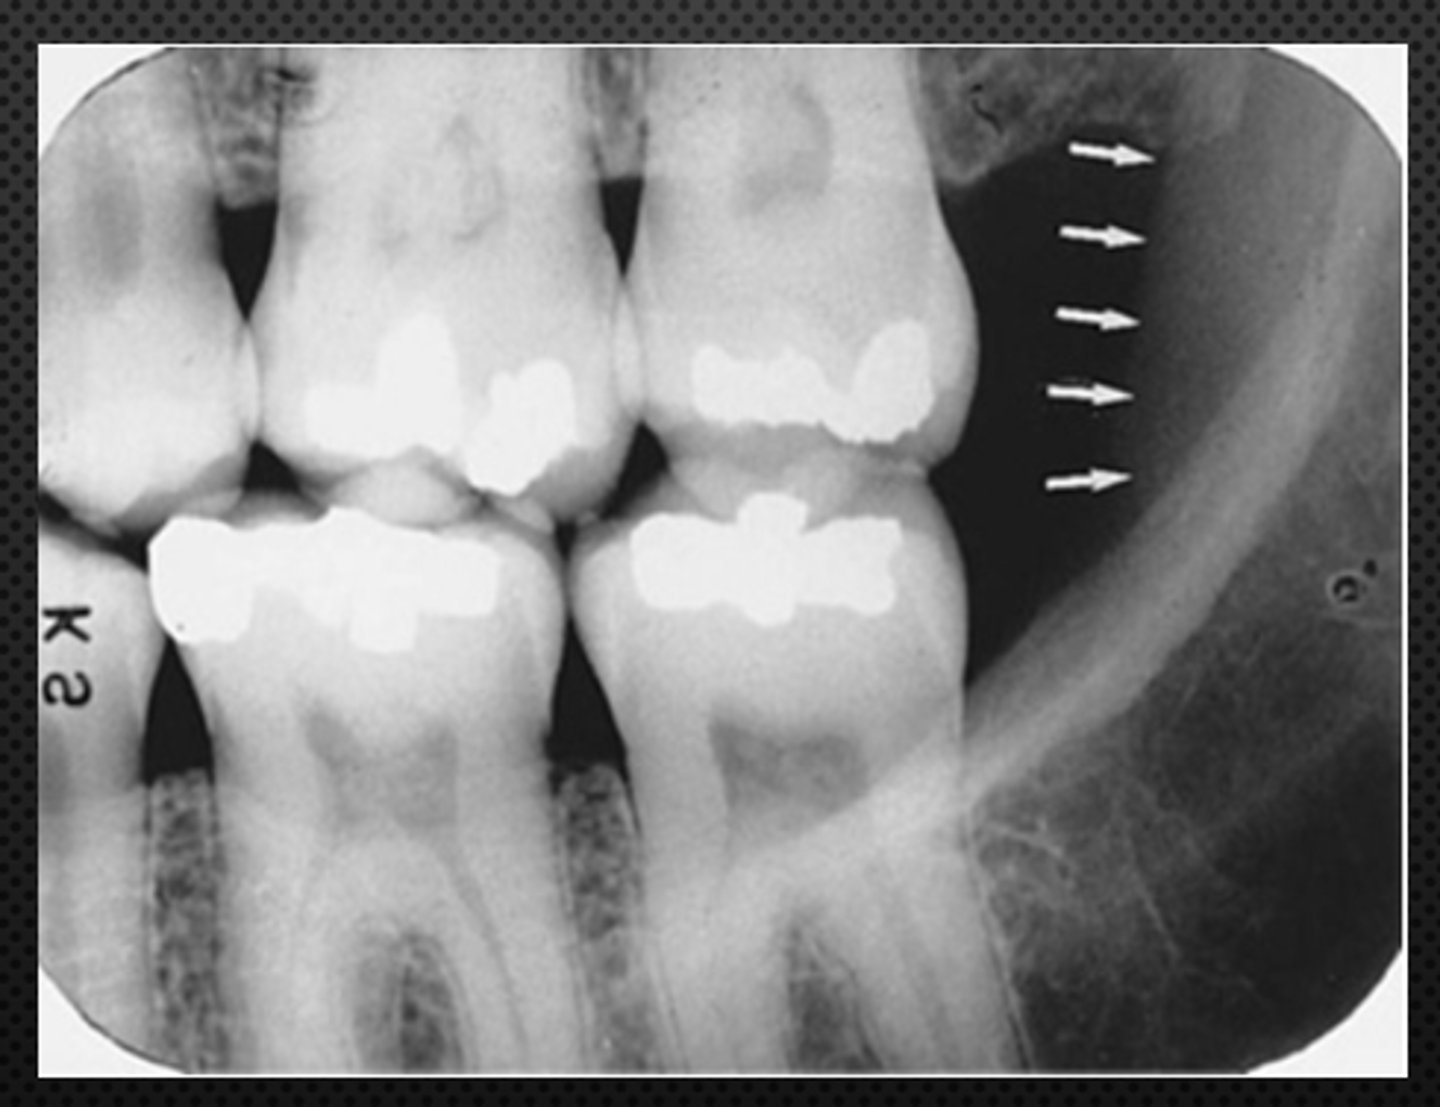

52

New cards

anterior border of the ramus

Name the structure the white arrow is pointing to.

<p>Name the structure the white arrow is pointing to.</p>

53

internal oblique ridge or mylohyoid ridge

Name structure the black arrow is pointing to.

<p>Name structure the black arrow is pointing to.</p>

54

Submandibular fossa

Name the radiolucent area indicated by the arrows

<p>Name the radiolucent area indicated by the arrows</p>